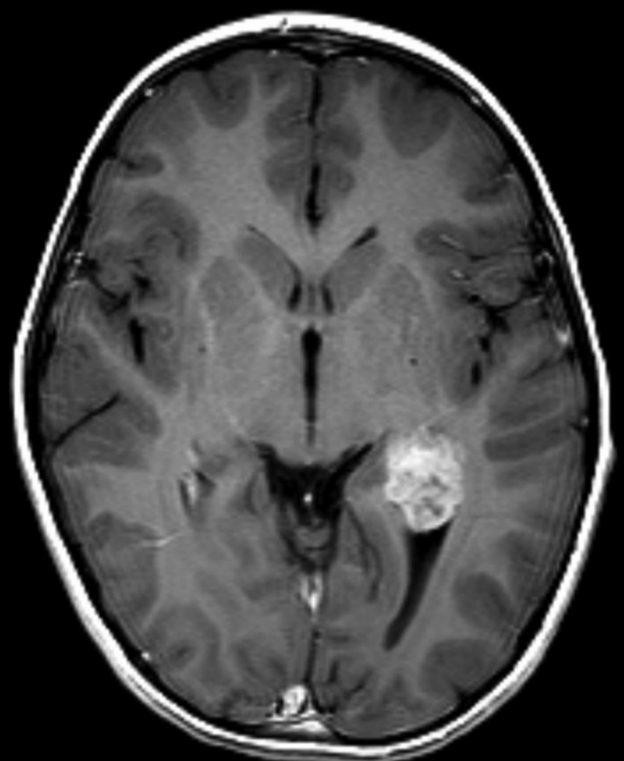

What is shown there ? I am a a medical student Please could somebody help ?

I think its tumor